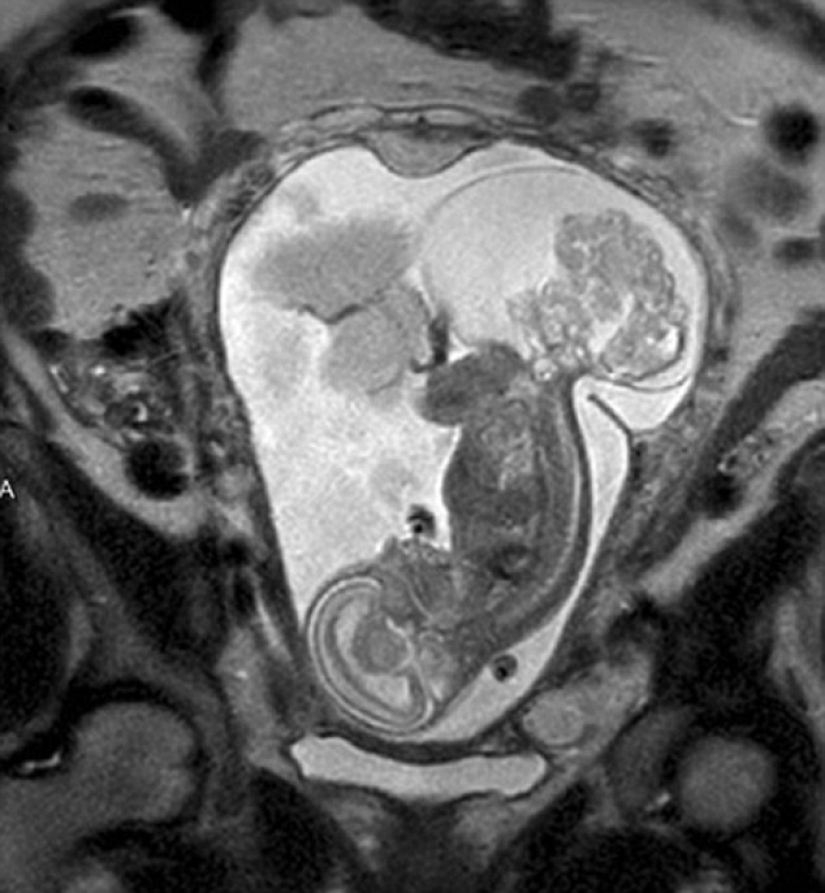

Cuando una residente de Texas, Margaret Bomer, hizo otro ultrasonido en la semana 16 de embarazo, los médicos le dijeron que el niño tenía un tumor en el área del cóccix. La única esperanza de salvación era una operación durante la cual los médicos tuvieron que abrir el útero y extraer un feto que pesaba 538 g durante 20 minutos, y luego devolverlo. Las posibilidades de la chica eran 50/50.

Para cuando los médicos obtuvieron el permiso para la operación, Lynley tenía aproximadamente 24 semanas de edad y el tumor era del tamaño del feto. La operación duró cinco horas, pero según el Dr. Kass, la parte que concierne al niño dura solo unos 20 minutos. La mayoría de las veces se tarda en abrir el útero. Tan pronto como los cirujanos llegaron al bebé, lo levantaron para que colgara en el aire. "De hecho, el feto resulta estar afuera literalmente, todo el líquido amniótico fluye, y esta es una vista realmente impresionante", dice el médico.

Durante la operación, el corazón de Lynley se desaceleró casi hasta detenerse por completo, pero su vida fue apoyada por un especialista separado mientras los cirujanos cortaban la neoplasia. Cuando hicieron todo lo que pudieron, los médicos volvieron a colocar a Lynley en el útero y la cosieron lo más fuerte posible. "Es como un milagro cuando puedes abrir el útero, coserlo de nuevo y todo sigue funcionando", dice el Dr. Cass.